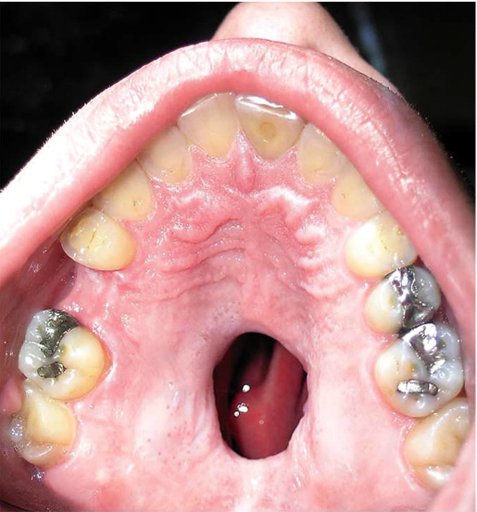

Τρύπα μπορεί και συχνά συμβαίνει να ανοίξει στον ουρανίσκο του στόματος. Το ιδιαίτερα εθιστικό ναρκωτικό προκαλεί αγγειοσυστολή. Οι αρτηρίες συστέλλονται, η κυκλοφορία του αίματος περιορίζεται και φτάνει λιγότερο οξυγόνο στους ιστούς του ουρανίσκου. Με λιγότερο οξυγόνο η μαλακή υπερώα ατροφεί και συρρικνώνεται με αποτέλεσμα να δημιουργηθεί η διάτρηση (τρύπα στη φωτογραφία). Τη φωτογραφία ενός ασθενή του με διάτρηση υπερώας ανέβασε στο facebook ο γιατρός Howard Farrann με την ελπίδα να αποτρέψει όσο περισσότερους μπορεί από τη χρήση ναρκωτικών. Η φωτογραφία, που έχει κοινοποιηθεί ήδη 58.000 φορές, έγινε γρήγορα viral στο Facebook και έχει συγκεντρώσει πάνω από 6.000 like.

Η διάτρηση του ουρανίσκου δεν απειλεί τη ζωή του ασθενούς, αλλά προκαλεί δυσκολίες στην ομιλία και στην κατανάλωση τροφών και υγρών.